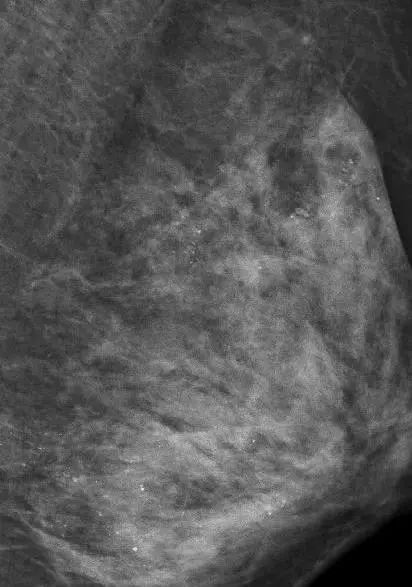

医生在对她的左侧乳房进行乳腺X线检查时,发现里面全部都是细小如沙子一样的钙化灶,布满整个乳腺。

在X光片下,朱女士的乳腺里满是星星点点的钙化灶

图片来源微博截图